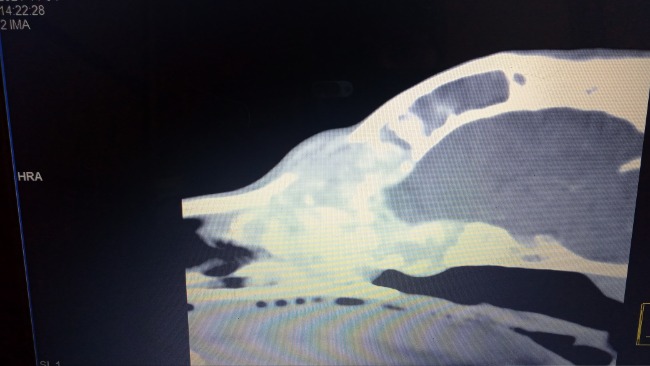

Ogi kichał od początku. Kichał strasznie. Z noska wyciekały mu gluty we wszystkich kolorach - od białych, żółtych, zielonych po brunatne. Aż zaczął kichać krwią. Próbowaliśmy go leczyć antybiotykami, sterydami, robiliśmy posiewy, był na zabiegu rinoskopii, który nic nie wykazał. Zdecydowaliśmy się na tomografię komputerową, która niestety pokazała nam ogromną zmianę. Nowotwór zajmuje prawie całą przestrzeń w nosie, przebija się do mózgu i gałek ocznych. Zniszczył też kość między oczami do tego stopnia, że pojawił się tam odstający guz.